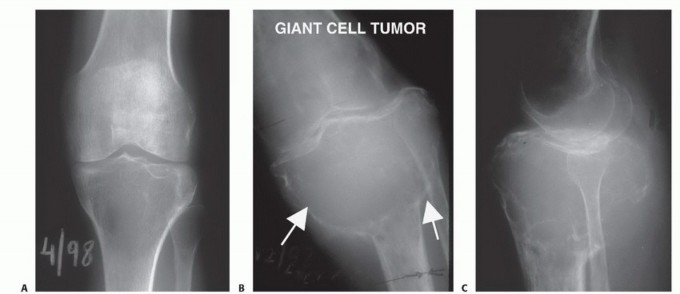

صورة شعاعية تظهر ساركوما عظمية في قصبة الساق القريبة لمريضة تبلغ من العمر 17 عاماً.

صورة شعاعية توضح ورماً عظمياً في قصبة الساق القريبة.

صورة شعاعية تظهر ورماً خلوياً عملاقاً في قصبة الساق القريبة.

صورة مقطعية توضح الورم الذي يملأ مشاش قصبة الساق القريبة.

صورة مقطعية أخرى للورم في قصبة الساق.

صورة شعاعية جانبية توضح ساركوما عظمية في قصبة الساق القريبة.

صورة بالرنين المغناطيسي تظهر مدى امتداد الورم داخل النخاع العظمي.

صورة شعاعية تظهر تدميراً قشرياً وامتداداً للأنسجة الرخوة للورم.

صورة مقطعية توضح تدميراً قشرياً وامتداداً للأنسجة الرخوة للورم.